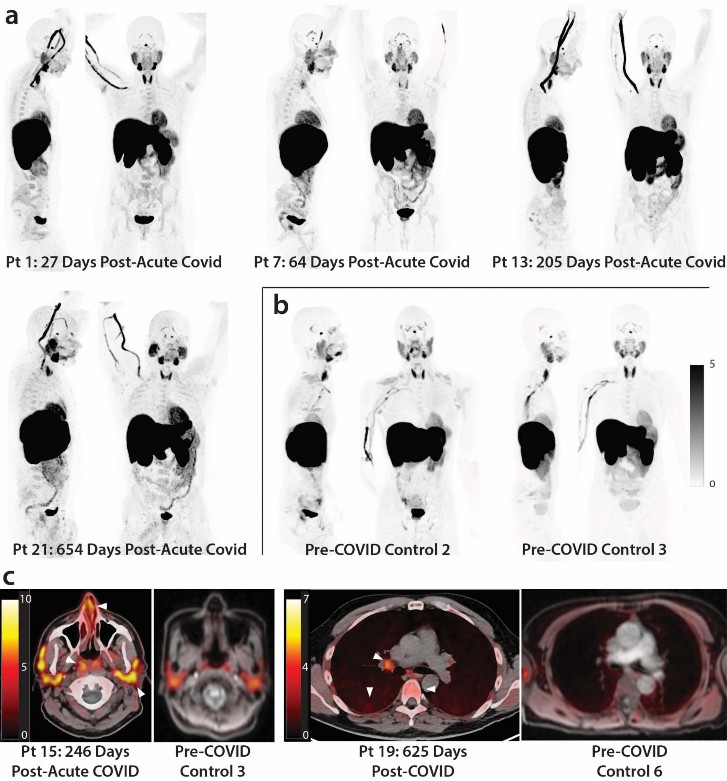

- As shown in Figs 1 & 2, significantly higher SUVmax and SUVmean values were observed across a

- variety of anatomic regions and tissue types in post-acute COVID participants compared with uninfected

- controls using two-tailed Kruskal-Wallis tests adjusting for false discovery rates within specific tissue

- regions (e.g., lymphoid tissues, glandular tissue, vascular, spinal cord, etc.). Maximum Intensity Projections

- (MIP) of PET data from all post-acute COVID and pre-pandemic control participants are shown in

- Supplemental Fig 1. Although [18F]F-AraG uptake was low overall in brain and spinal cord tissues (i.e .,

- SUVmax and SUVmean <1), significantly higher SUVmax and SUVmean were identified in the thoracic

- spinal cord and cauda equina (at the level of the fourth lumbar vertebra) and higher SUVmean was

- identified in the brain stem (pons) as in Fig 2. The CNS choroid plexus is known to express high levels of

- ACE-2, but this region had high background uptake and there were no differences between post-acute

- COVID cases and pre-pandemic controls. Significantly higher levels of [18F]F-AraG uptake (SUVmax and

- SUVmean) were also observed in the aortic arch, pulmonary artery and lower lung lobes compared with

- pre-pandemic controls. Significant increases in [18F]F-AraG uptake were observed in nasal turbinates

- (SUVmax and SUVmean), hilar lymph node regions (right-sided; SUVmax), proximal colon wall (SUVmax),

- rectal wall (SUVmax and SUVmean), lumbar (SUVmax) and iliac crest (SUVmax and SUVmean) bone

- marrow and pharyngeal tonsils (SUVmax). Although not achieving statistical significance, increased tracer

- uptake was observed in parotid glands and right heart ventral wall in post-acute COVID participants

- compared to pre-pandemic controls ( Fig 2). Uptake in the liver (a metabolic and excretory organ for

- [18F]F-AraG), abdominal adipose tissue, and quadriceps muscles were similar across all participants. No

- significant differences in SUV were observed in testes, penile tissue, prostate, or uterine tissue, although

- sample size was limited for these comparisons ( Supplemental Fig 2).

Impact of time between acute COVID-19 and PET imaging on biodistribution of [

18 F]F-AraG.- We performed imaging over a span of nearly two and a half years following COVID-19 symptom onset to

- determine the duration of T cell activation states in tissues. Fig 3a shows [18F]F-AraG SUVmax for tissues

- of interest stratified by timing of PET imaging before or after 90 days following initial COVID-19 symptom

- onset. We observed modestly decreased uptake in spinal cord and colon/rectal wall ROIs in participants

- imaged beyond 90 days following COVID-19 symptom onset, but SUVs in these later-imaged individuals

- remained significantly elevated compared to pre-pandemic controls, with the exception of the right colon

- wall. When stratified by time since initial COVID-19 symptom onset, [18F]F-AraG uptake in the right

- ventricle wall was significantly higher in post-acute COVID participants compared with pre-pandemic

- controls ( Fig 3a). Of note, no significant correlations between [18F]F-AraG uptake in any tissue ROI and

- time from initial infection to PET imaging in those imaged beyond 90 days were observed (all P>0.05 by

- two-tailed Spearman tests).